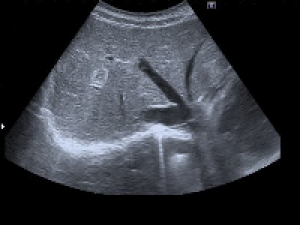

L’échographie utilise des ultra-sons. Ils sont produits par une sonde placée sur la peau du patient ; ils passent à travers la peau grâce à un gel de contact et sont réfléchis partiellement par les organes qu’ils traversent.

Les ultra-sons réfléchis sont enregistrés par la sonde et permettent de créer l’image en coupe visible sur l’écran.

Echographie abdominale

 Restez à jeun de la veille au soir pour les examens réalisés le matin, du petit déjeuner (léger) pour les rdv l'après midi